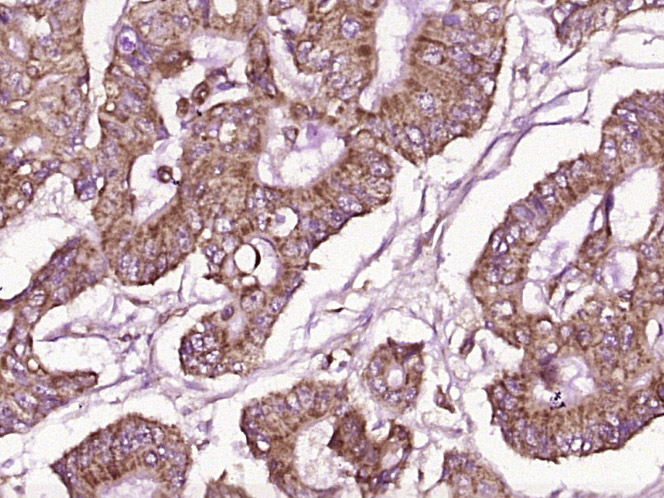

Paraformaldehyde-fixed, paraffin embedded (human colon carcinoma); Antigen retrieval by boiling in sodium citrate buffer (pH6.0) for 15min; Block endogenous peroxidase by 3% hydrogen peroxide for 20 minutes; Blocking buffer (normal goat serum) at 37°C for 30min; Antibody incubation with (GPA33) Polyclonal Antibody, Unconjugated (bs-1226R) at 1:400 overnight at 4°C, followed by operating according to SP Kit(Rabbit) (sp-0023) instructionsand DAB staining.